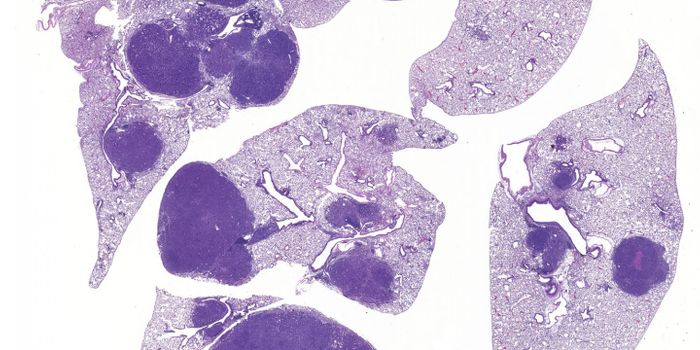

JUL 08, 2021Genetics & GenomicsChildren with Down syndrome have a significantly higher likelihood myeloid leukemia occurring in the first five years of ...